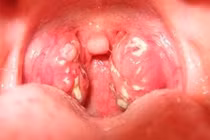

Viêm amidan là bệnh lý khá phổ biến ở mọi lứa tuổi, trong đó có trẻ nhỏ. Trẻ bị viêm amidan tái phát ở trẻ em nếu không được xử lý đúng cách có thể khiến bệnh diễn biến nặng và gây biến chứng nguy hiểm.

(khoahocdoisong.vn) - Từ đầu năm đến nay Bệnh viện Nhi T.Ư đã phẫu thuật cho hơn 400 trẻ bị viêm amidan, trong đó phần lớn do amidan quá phát. Bệnh gây nhiều biến chứng nguy hiểm, làm ảnh hưởng nhiều đến kết quả học tập, sức khỏe và chất lượng cuộc sống của trẻ... nên cần nhận biết chữa trị sớm.